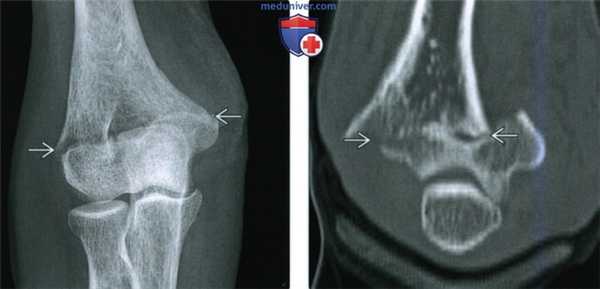

(Слева) На снимке определяется чрезмыщелковый перелом плечевой кости у женщины 63 лет после падения на выпрямленную руку. Линия перелома пересекает оба мыщелка, но не переходит на суставную поверхность. Имеется незначительное медиальное смещение дистального отломка, что является частой находкой при таких травмах.

(Справа) На фронтальной компьютерной томограмме с реформатированием без контрастирования у этой же пациентки подтверждается чрезмыщелковый ход перелома и отчетливо видно медиальное смещение дистального отломка. Кроме того, данные КТ подтверждают сохранность суставной поверхности плечевой кости.